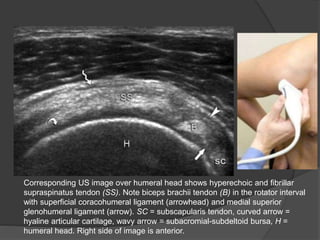

Corresponding US image over humeral head shows hyperechoic and fibrillar

supraspinatus tendon (SS). Note biceps brachii tendon (B) in the rotator interval

with superficial coracohumeral ligament (arrowhead) and medial superior

glenohumeral ligament (arrow). SC = subscapularis tendon, curved arrow =

hyaline articular cartilage, wavy arrow = subacromial-subdeltoid bursa, H =

humeral head. Right side of image is anterior.